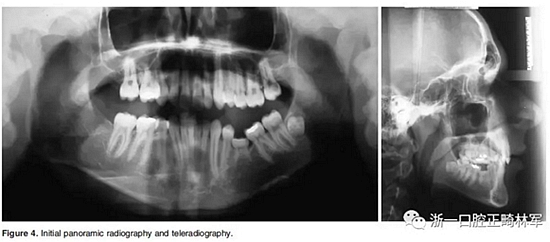

4.影像檢查:右上前磨牙和左下第二前磨牙缺失(Figure 4)。在另一名牙齒矯正醫(yī)師治療4年后,患者在19歲時(shí)被轉(zhuǎn)診給我們。他的咬合特征與他的初始狀態(tài)非常相似(Figure 5)